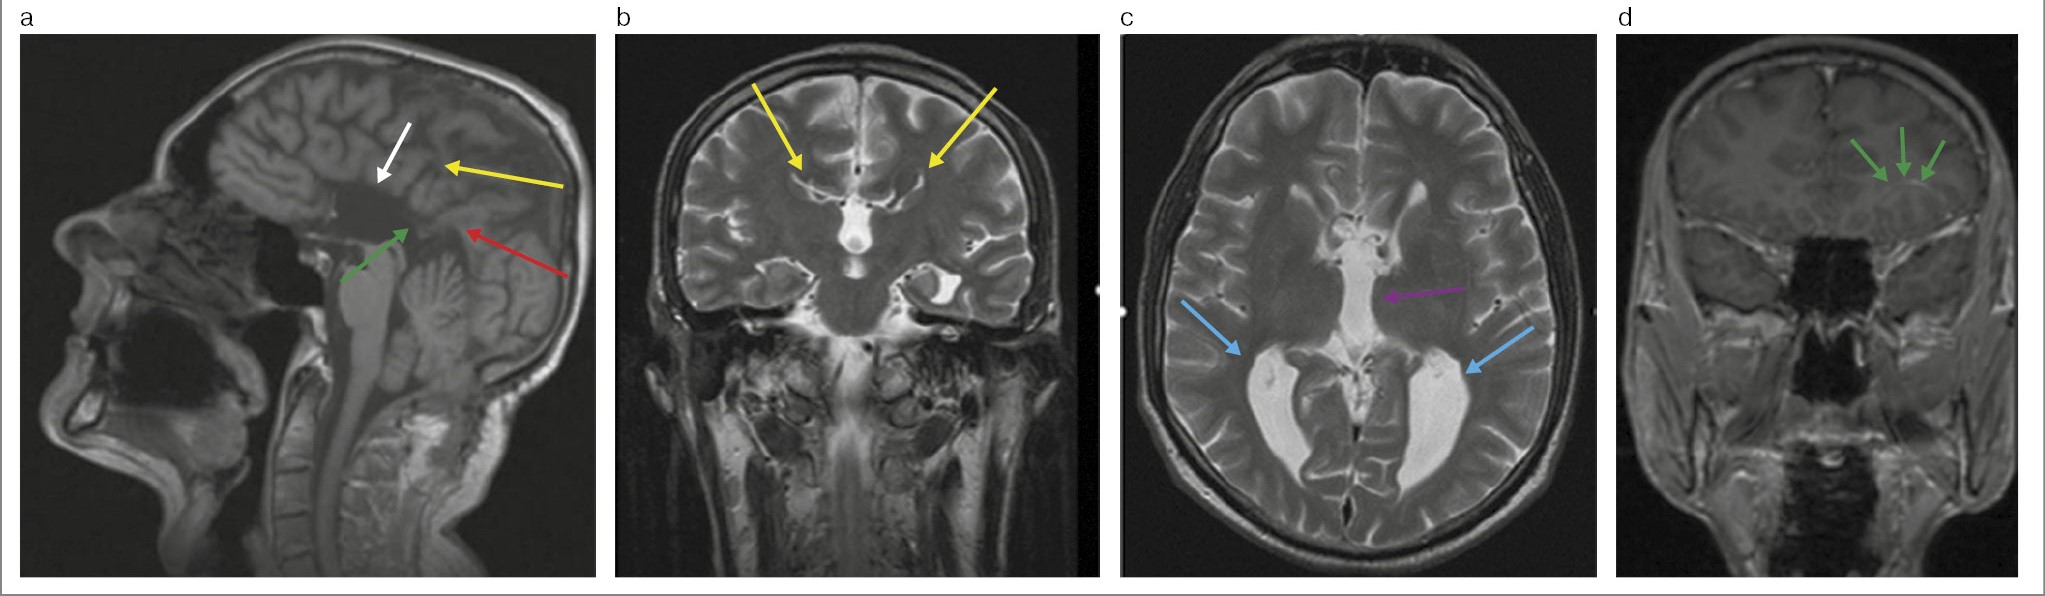

Мальчик Б., 12 лет. Жалоб нет. При тщательном сборе анамнеза у матери стало известно, что ребенок рос и развивался соответственно возрасту. Хронических заболеваний нет. Положительный семейный анамнез относительно наследственных заболеваний отсутствует. Каких-либо токсических воздействий, а также инфекций во время беременности мать не отмечает. Употребление алкоголя в этот период отрицает. Успеваемость в школе хорошая. Затруднений в обучении нет. Мальчик успешно занимается боксом. В своей весовой категории он один из лучших спортсменов. При проведении медицинской диспансеризации, с учетом вида спорта, выполнена МРТ ГМ, по результатам которой очаговых и диффузных изменений вещества ГМ не выявлено. В сагиттальной проекции все отделы МТ, кроме валика, не визуализируются. Прозрачная перегородка отсутствует. Имеется расширение крыши III желудочка. Межполушарная борозда спускается вниз до крыши III желудочка. Определяется аномальная поясная извилина.

Визуализируются пучки Пробста. Гиппокамп закруглен в аксиальных срезах. Боковые желудочки имеют параллельный ход, расстояние между ними – 44 мм, III и IV желудочки не расширены.

Передние рога латеральных желудочков имеют вертикальный ход, длина правого и левого составляет 23 и 24 мм соответственно – симптом «шлема викинга».

Миндалины мозжечка расположены на уровне большого затылочного отверстия, не выступая за его пределы.

Заключение: МРТ-картина частичной АМТ с сохранением валика и ленточной извилины (рис. 2, 3).

Рис. 2. Больной Б., 12 лет. МРТ ГМ: a – Т1-взвешенное последовательное изображение: в сагиттальной плоскости: отсутствие вентральных отделов МТ (красная стрелка); валик (МТ) и ленточная извилина (желтая стрелка); расширение крыши III желудочка (голубая стрелка); аномальная поясная извилина (зеленая стрелка); b – Т2-взвешенное последовательное изображение в коронарной плоскости: симптом «шлем викинга» – поясная извилина вывернута в виде суженных и удлиненных лобных рогов.

Рис. 3. Больной Б., 12 лет. МРТ ГМ: Т2-взвешенное последовательное изображение в аксиальной плоскости: симптом «гоночного автомобиля» – расширенное расстояние между латеральными желудочками (красные стрелки); миелинизированные пучки Пробста располагаются медиальнее боковых желудочков (желтые стрелки).

Больной консультирован неврологом. Физическое развитие – без особенностей, нарушения речи отсутствуют. Признаков неврологического и когнитивного дефицита нет. Выполнена ЭЭГ. Изменений биоэлектрической активности не выявлено. Поставлен окончательный диагноз «частичная АМТ, отсутствие прозрачной перегородки».